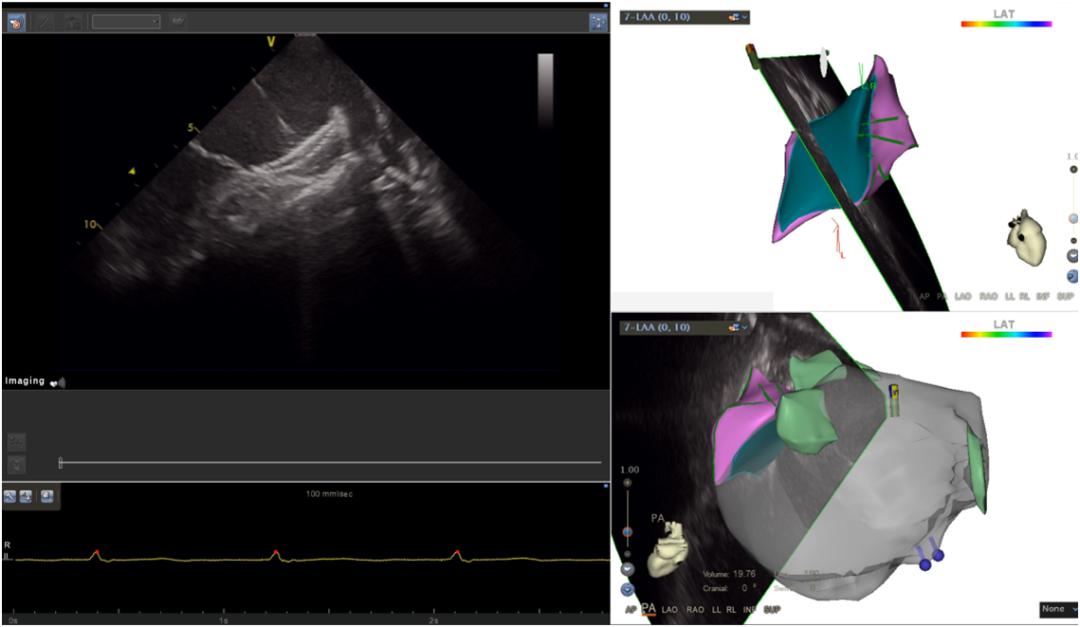

经过前期的充足准备,在仁济医院心内科主任卜军教授、西院徐瑾教授和宝山分院黄剑锋教授团队共同合作下手术成功实施。在心腔内超声(ICE)和CARTO3三维标测系统指引下,团队无缝衔接,完美配合顺利开展了左心耳封堵和房颤导管消融手术。术后,在医务人员的精心治疗及护理下,目前患者身体健康良好。

心腔内超声(ICE),即心腔内超声成像技术,是一项术中实时超声监测技术,临床应用优势明显,尤其是老年患者,行左心耳封堵术的同时可以避免全麻后遗症、术后难苏醒等问题。且能保证患者在比较平静的状态下顺利进行手术。同样,ICE也适用于食道超声检查有禁忌的患者。房颤“一站式”介入治疗的患者,ICE还能代替多极导管进行左房精确建模,提高手术安全性和减少射线量。